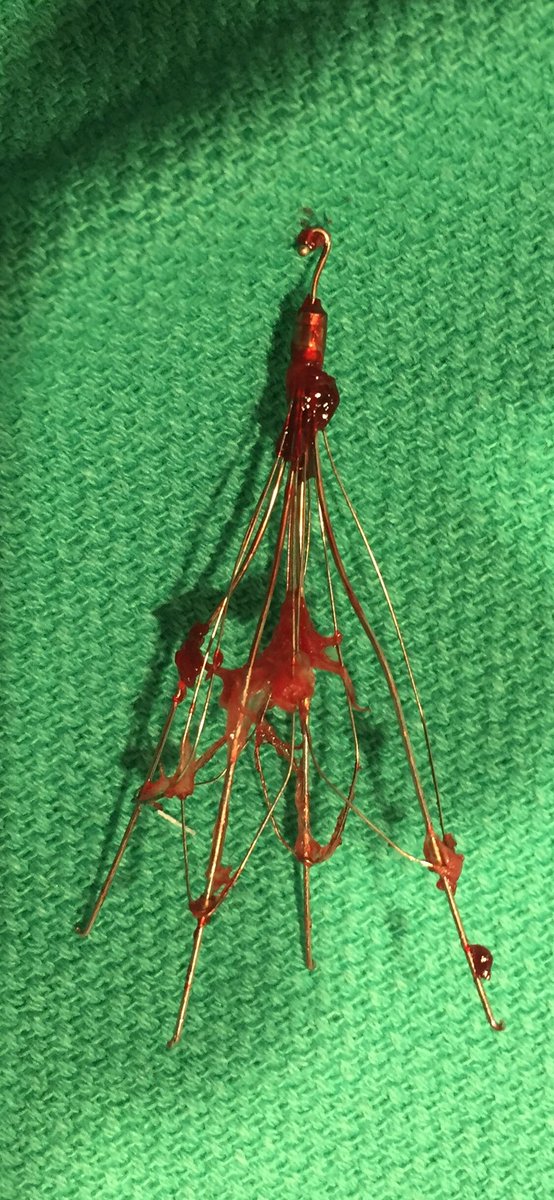

When the loop fails to engage...Clover snare kit + 💪🏻 #filterOUT. #GTFO #irad @CookMedical @SIRRFS @Drshiloh @SDhandMD @amdevane